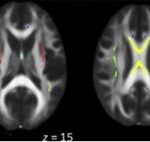

Se pueden mencionar al respecto los estudios que han encontrado en pacientes dependientes al alcohol una disminución del volumen de sustancia gris en el área de la corteza frontal, el hipocampo y el tálamo. El volumen de las sustancias blanca y gris también se puede ver disminuido en el área periventricular, la protuberancia y el cerebelo. Estos déficits de volumen también se han localizado en la corteza prefrontal dorsolateral derecha, ínsula anterior derecha, en el núcleo accumbens y en la amígdala izquierda(16) (ver Imagen 1).

Asimismo, como se indicó previamente, a través de la TC también se puede observar el deterioro de la microestructura cerebral por adicción al alcohol. El abuso de esta sustancia altera cinco fibras del cerebro, como el cuerpo calloso, el fondo de saco, la cápsula externa, el cíngulo circunvolución y el fascículo longitudinal superior, las que están involucradas en funciones como el procesamiento visoespacial y del lenguaje, la comunicación interhemisférica, la memoria, el procesamiento emocional, la toma de decisiones y la integración sensorial(16) (ver Imagen 2).